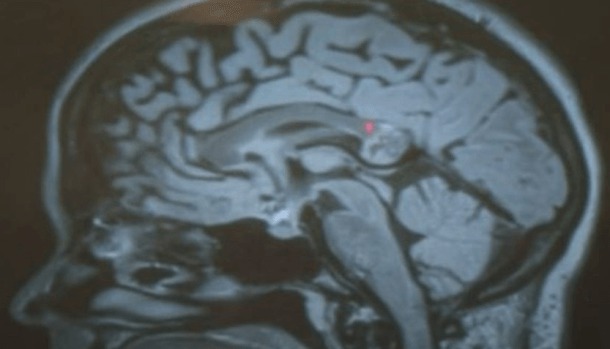

Elle avait l’embryon de son jumeau dans le cerveau

La chose a été découverte après qu’une jeune femme d’origine indienne vivant dans l’état de l’Indiana aux USA, se soit sentie mal à plusieurs reprises. Après avoir consulté des médecins, il a été découvert une tumeur. Yamini Keranam puisqu’il s’agit d’elle, a alors du subir une intervention pour retirer la tumeur et c’est lors de l’intervention que son chirurgien, spécialiste dans le domaine, a réalisé en voyant les cellules, qu’il s’agissait d’une tumeur embryonnaire.